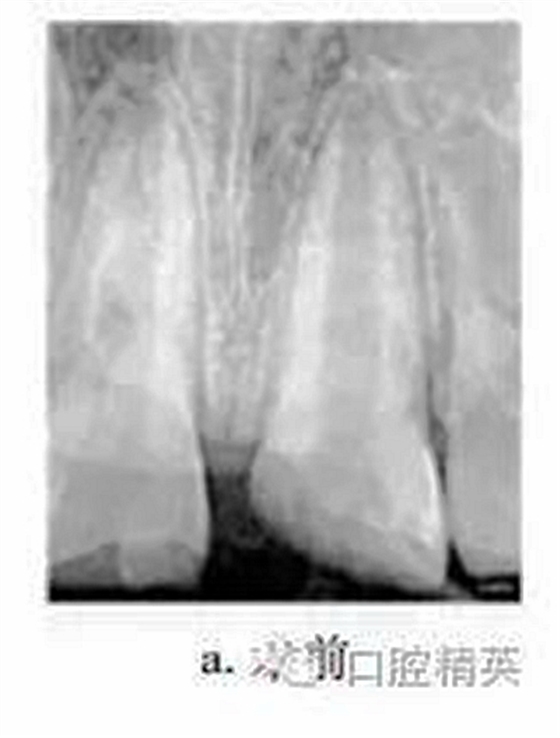

患者男,10歲。2011-06因上頜中切牙外傷就診于我院牙體牙髓病科。患者自述3d前患牙外傷,冷熱刺激敏感,但未行治療。檢查:11牙冠近中切角缺失,切緣釉質(zhì)缺損,無(wú)松動(dòng),探敏感,叩(+),冷熱無(wú)明顯不適;21牙冠近中斜折,邊緣銳,髓腔暴露,探診出血,探痛明顯,牙髓電活力測(cè)試(-),叩(+),無(wú)松動(dòng),牙齦未見(jiàn)異常,上唇腫脹。X線片示:21冠部缺損及髓,牙周膜腔增寬,根端管壁呈平行狀,根尖孔未閉合(圖a)。診斷:11釉質(zhì)缺損;21冠折。